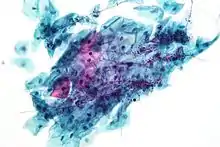

| Tinción de Papanicolau | Permite ver la cromatina con mucha claridad.

|

Se utiliza para diferenciar células en muestras de secreciones biológicas (esputo, LCR, orina, etc.) y en raspados y biopsias. Permite distinguir con relativa facilidad células con transformaciones neoplásicas, levaduras y bacterias. |